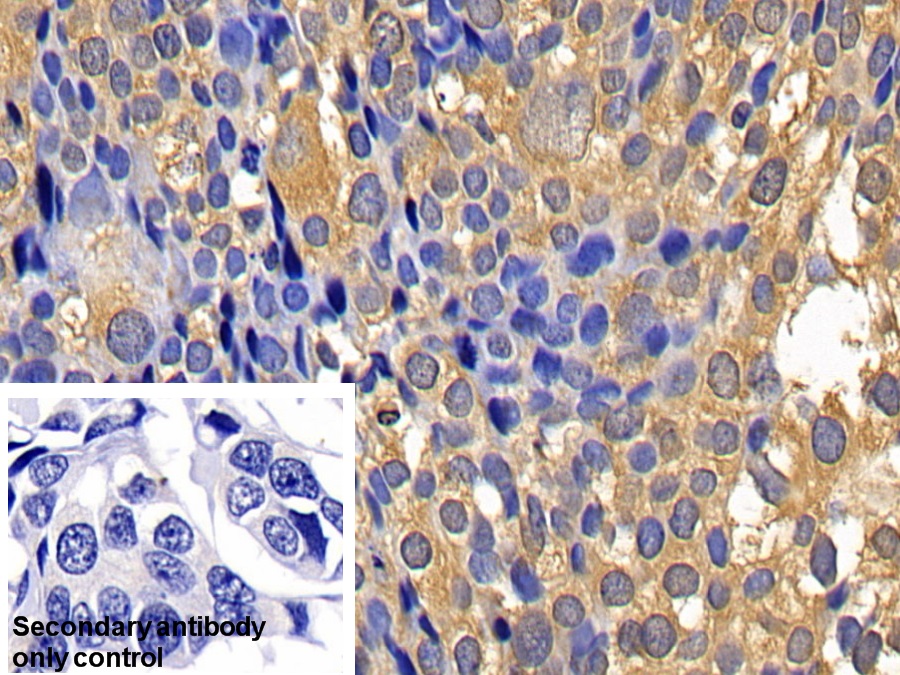

Использование высококачественных первичных антител является неотъемлемым условием получения точных и воспроизводимых результатов в современных научных исследованиях. Например, в рамках онкологического исследования удалось достоверно идентифицировать экспрессию белка PD-L1, что сыграло ключевую роль в оценке потенциальной эффективности иммунотерапии. Применение надежных антител обеспечило стабильность сигнала и высокую специфичность детекции, что позволило получить данные, пригодные для публикации в рецензируемых научных изданиях.

Использование некачественных антител, напротив, сопряжено с рядом существенных рисков. Низкая специфичность может привести к неселективному связыванию с незапланированными молекулами, а недостаточная чувствительность — к слабому или нестабильному сигналу. Такие проблемы не только снижают достоверность результатов, но и могут стать причиной неверной интерпретации данных, что особенно критично в условиях фундаментальных и прикладных исследований.